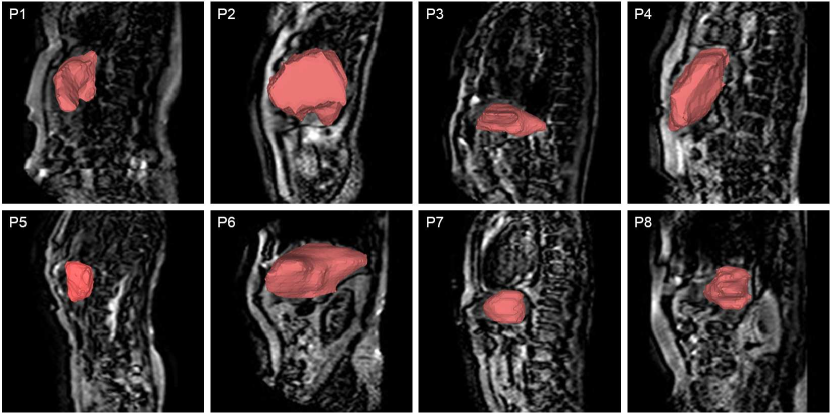

The eight metastatic patients have significantly different liver shapes and deformations, as shown in Fig. 3 and the optimal scan planes for each patient were very different. For this reason, for the metastatic liver, the optimal scan plane was determined patient-specifically with approximately 505050 informative vertices for each patient and this was used to slice the meshes in the 3D SSM. The sliced contours were projected onto the slicing plane with 2D coordinates to simulate 2D contours. A 2D SSM was constructed for each patient.

Refer to caption

Figure 3: The eight metastatic livers shown on their corresponding MR images.